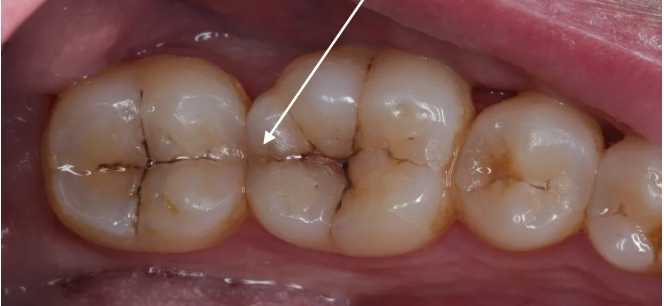

🔍 크랙치아란 무엇인가요?

크랙치아는 말 그대로 치아에 미세한 금이 생긴 상태를 말합니다.

눈으로 보기에는 괜찮아 보여도, 실제로는 치아 안쪽까지 균열이 진행된 경우도 많습니다.